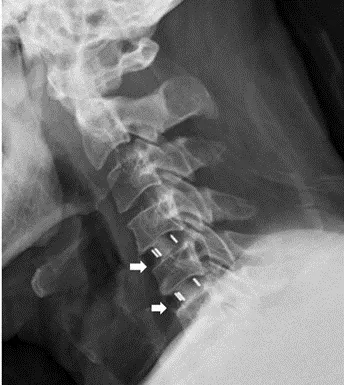

在等待健保審核衛材的期間,李元甫醫師安排頸椎的硬脊膜外注射,藉此來精準定位受影響的神經根,與此同時W先生也回報左上肢症狀有明顯的緩解。手術採微創方式,在顯微鏡的幫助下精準清除突出的第4/5及5/6兩節的頸椎椎間盤,在確認神經壓迫狀況已解除後放置椎間盤融合器,術後穿戴頸部護具。手術當天即可進食及下床活動,於術後第二天拔除引流管,在確認呼吸、吞嚥及神經學狀況沒有異常後,W先生於隔日辦理出院。

頸椎相關疾病雖然盛行率不如腰椎及膝關節,但影響的病人常是中壯年人口,此族群往往肩負家庭經濟重任,也是社會經濟發展的主力,若能用精準微創手術解決頸椎相關疾病,不僅可以讓病患重新拾回生產力,也可讓病患脫離藥石罔效的惡夢。W先生於回診時提到睡眠品質的提升,讓他更有信心回歸工作崗位,李元甫醫師在欣慰之餘,不忘提醒W先生須將頸部護具穿戴滿6週,如果要回職場,希望W先生能請公司安排較不費力的工作,在小心保護手術成果後,才能以滿血狀態繼續貢獻自己的勞動力。